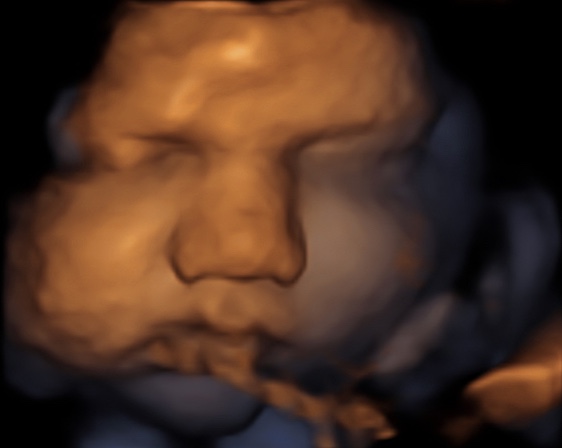

37 weken

Een echo na 37 weken.